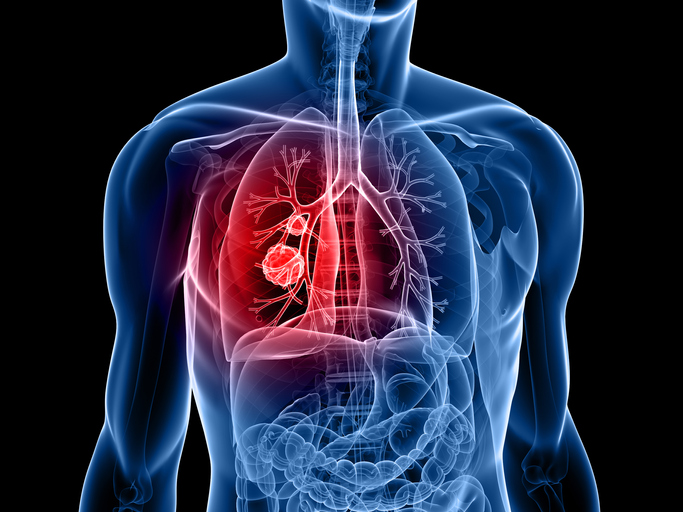

폐 건강 왜 중요한가?

폐와 기도 질환은 사람의 생명과 직결되는 호흡을 담당하고 있어 우리 인체에 가장 주요한 기관이기도 하지만 만성적인 질병으로 이어질수도 있어 무엇보다 예방이 중요합니다.